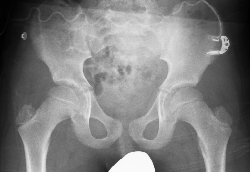

Orthopedic package

The orthopedic package is designed to give you full orthopedic functionality on your CombiDiagnost R90.